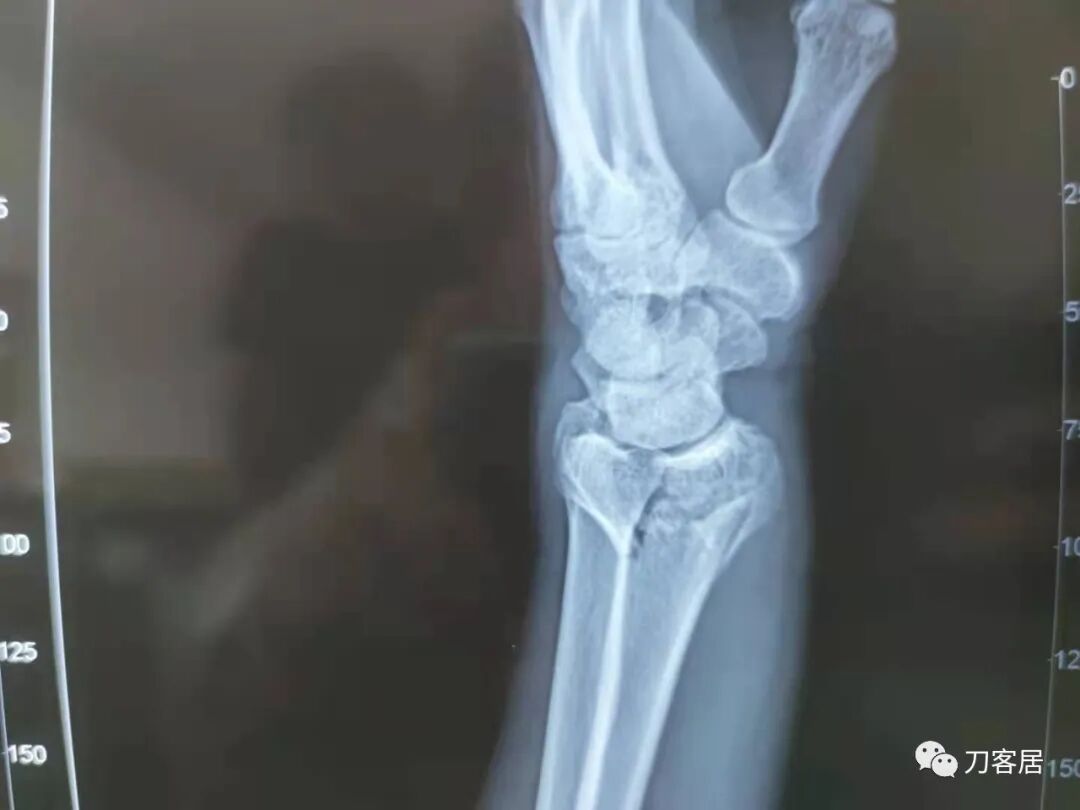

下面是这个6岁孩子,尺桡骨远端双骨折的术前及术后片子和外观照片。

2.  这个骨折处理起来也很简单,单纯的打石膏托或者中医的小夹板,或者正规的包括腕关节和肘关节的管型石膏外固定4周即可治愈该骨折。实在不行,如果这个孩子比较听话,不太调皮的话,用一本书,一个三角巾悬吊固定4周,都可以治愈该骨折。但是给这个患者用外固定架做了手术,而且桡骨远端的几颗克氏针距离骨折线太近,其中一枚克氏针进入到骨折间隙内。从这个术中图片来看,术者的外固定手术技术也有待于进一步的提高。毕竟术者应该还很年轻。从X线片来看,前臂及手的尺侧有不透光影,应该还使用了外固定石膏绷带托,而且我猜测应该是高分子的石膏绷带托,这个是纯属猜测,不一定是对的,不过如何解释前臂尺侧的不透光影呢?如果真是用了石膏绷带外固定的话,那为啥要做手术呢?外固定架术后就不该再用石膏绷带托辅助了。